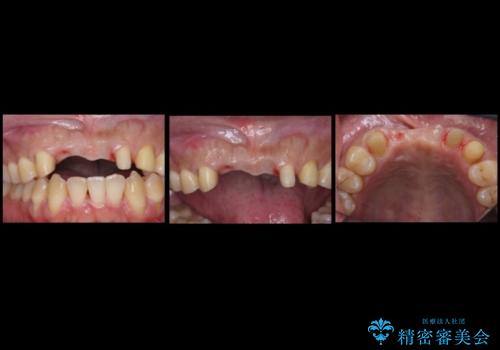

- 前歯のブリッジのやりかえおよび銀の詰め物をセラミックにしたいと来院。

過去に事故で前歯を折って、ブリッジにしたとのことでしたが、支台となる歯が持たない状況で、ブリッジを延長せざるを得ない状況でした。

左上1番は再根管治療を行いましたが途中で破折が確認されたため、抜歯しています。